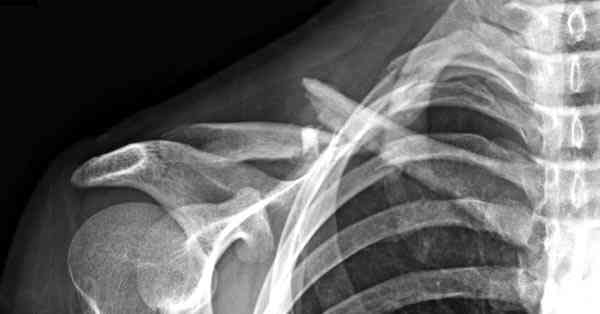

iГГШ> выполнения новокаиновой блокады дежурной бригадой выполнена закрытая

ГГШ> репозиция, наложены кольца Дельбе. Результаты репозиции показаны на

ГГШ> Результат стационарного лечения приведен на рентгенограмме (Xray_3).

Это картинка то есть через неделю после травмы, при выписке? Более чем приемлемо.